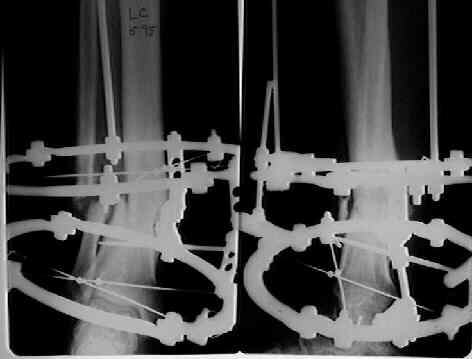

It seem a stiff pseudarthrosis. I will do a axial correction and lengthening if necessary with Ilizarov frame without any corticotomy. Probability of success will be 100% and relapse of infection 0%. You can see one case attached.

Best regards,

Nuno Craveiro Lopes

Almada - PORTUGAL